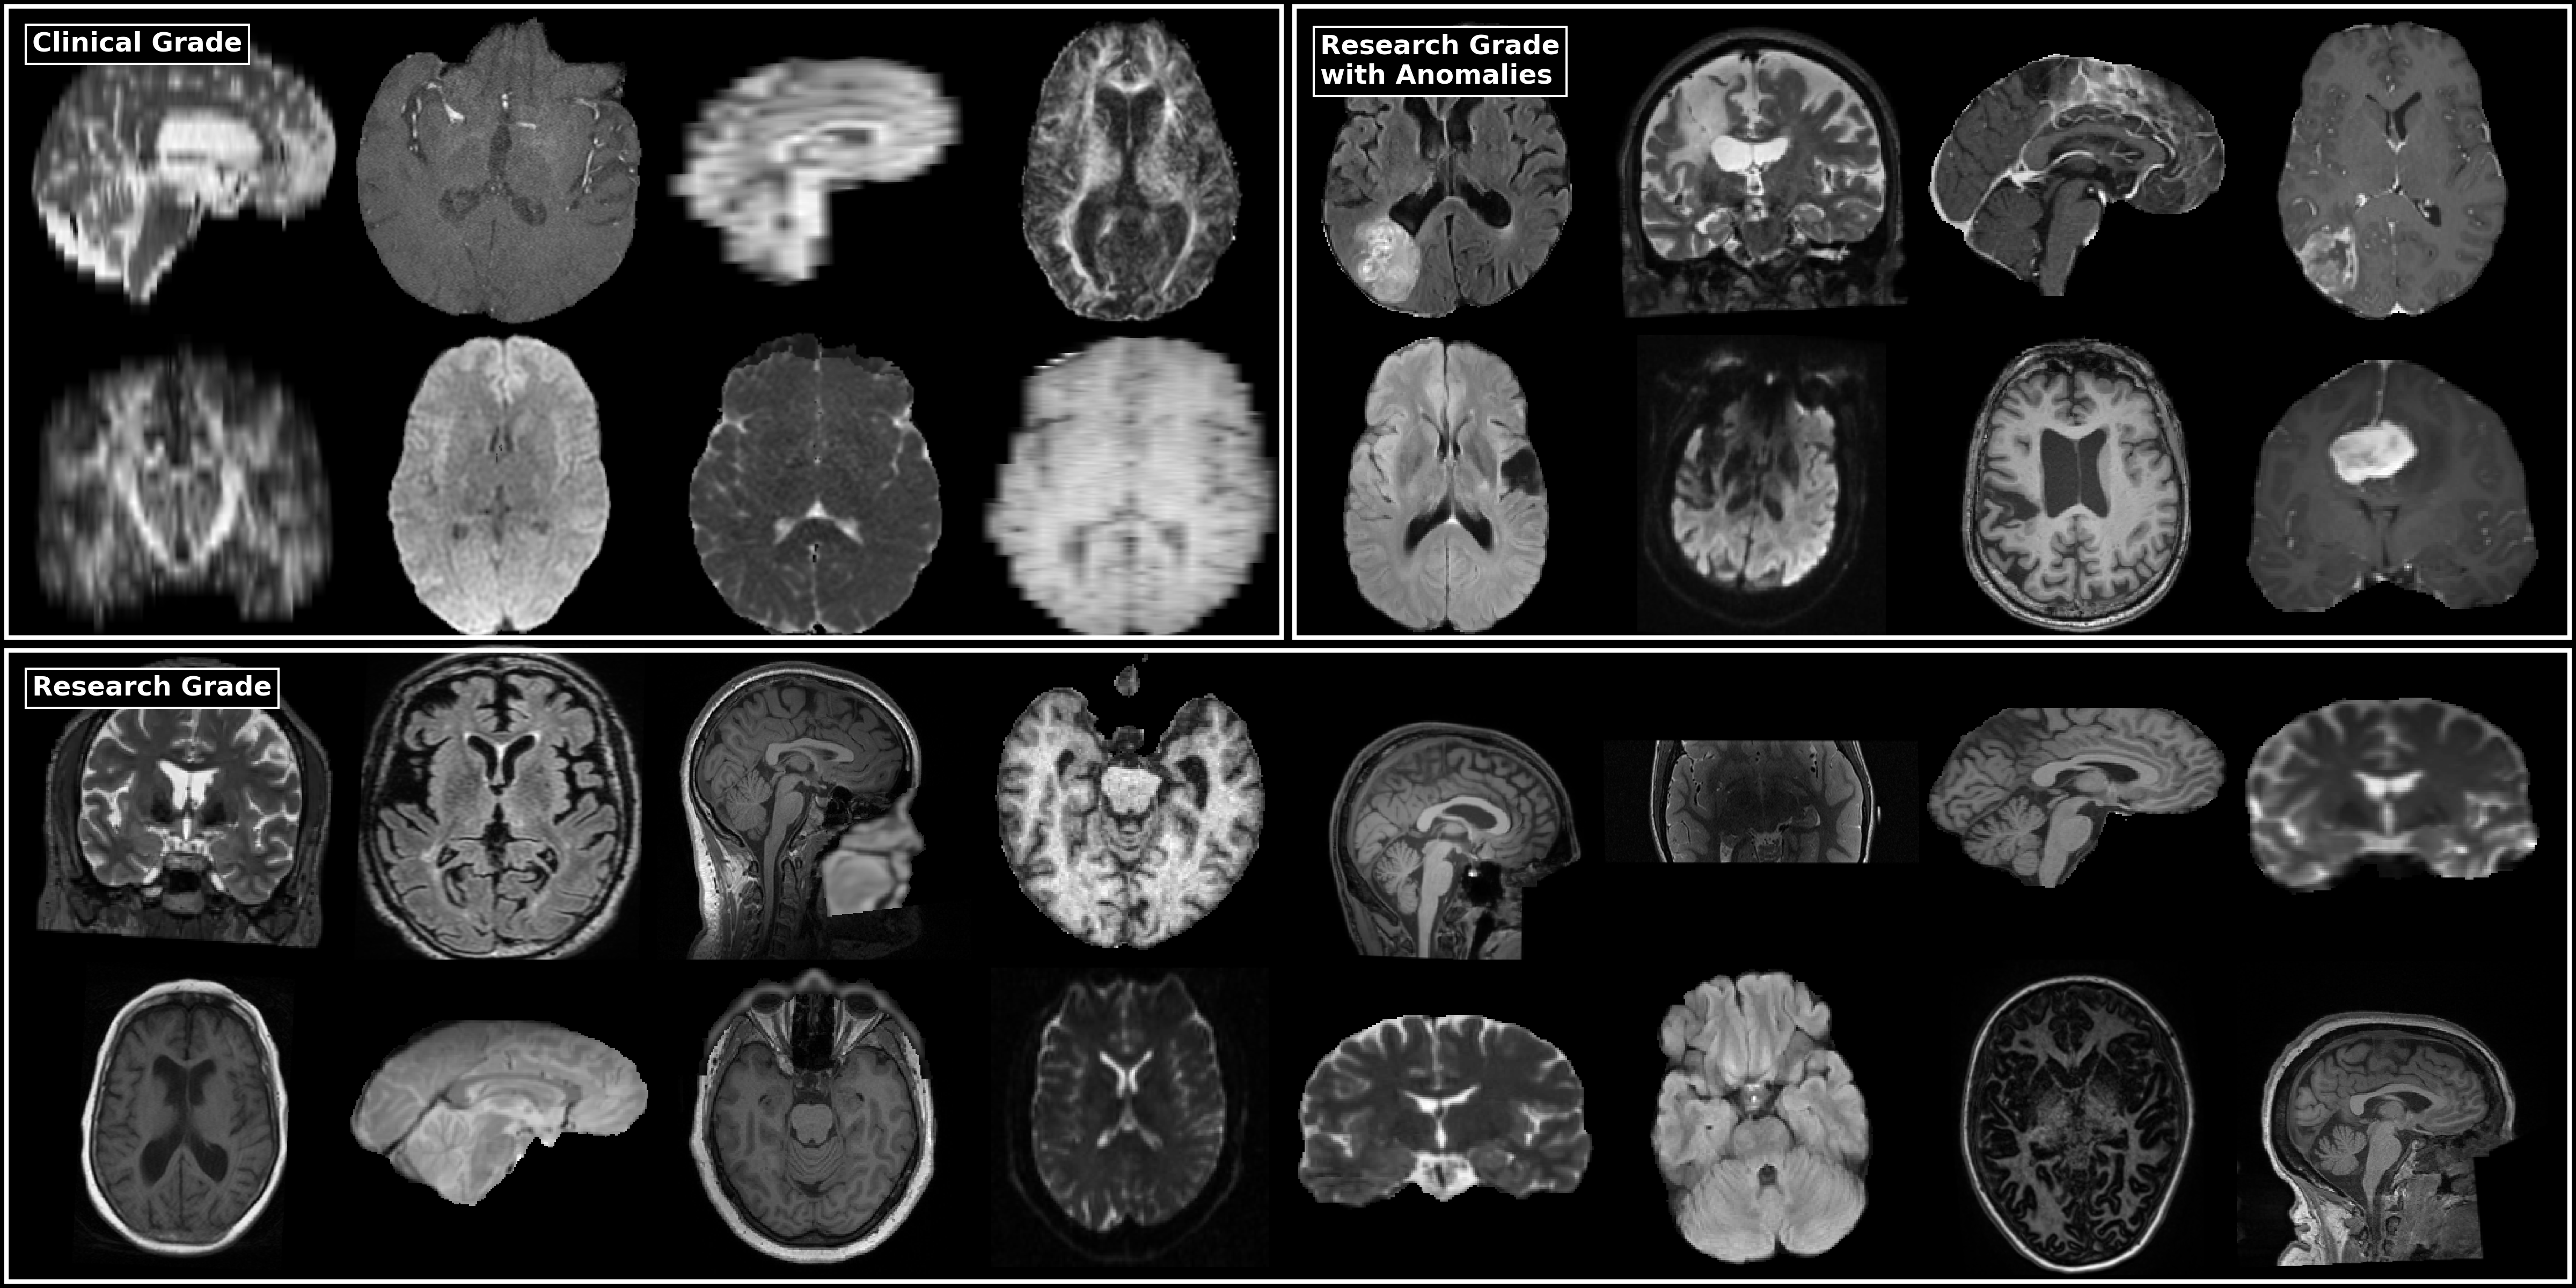

FOMO300K contains 318,877 scans from 82,678 MRI sessions and 59,969 subjects, aggregated from 920 publicly available sources. All available scans from each source were eligible for inclusion, except ex vivo scans, functional MRI, field maps, and computed tomography scans, which we excluded to prevent distribution shifts that could hinder SSL pretraining. No other exclusion criteria were applied. Table 2 summarizes the source datasets, listing the number of subjects, sessions, scans, MRI sequence types, and license. The largest contributions of FOMO300K come from HBN, HCP Wu Minn, Yale Brain Mets Longitudinal, and the OpenNeuro repository. Almost all datasets include T1-weighted structural MRI, while T2-weighted, FLAIR, and diffusion-weighted sequences are also widely represented. A visual overview of the dataset’s heterogeneity—in terms of image quality, modality, and pathology—is provided in Figure 1.

Figure 1: Representative examples from the FOMO300K dataset, illustrating the heterogeneity in image quality, MRI sequences, and the presence of brain anomalies.